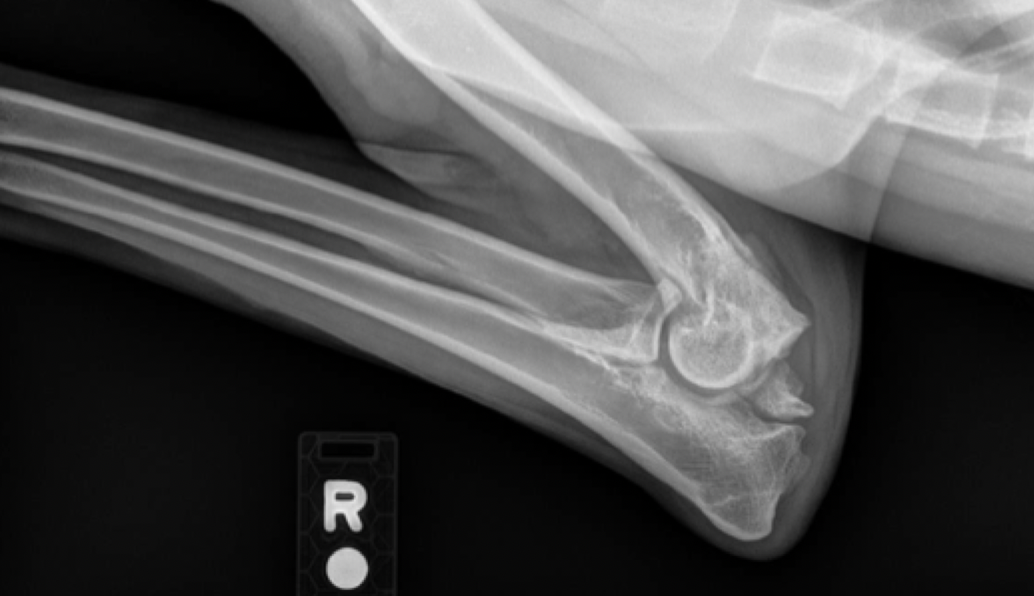

Flattening of the caudal humeral head (most common site)

due to Osteochrondritis Dissecans (OCD)

looks flatter bc cartilage is becoming thicker and thicker

will often be bilateral

large, fast growing dogs are predisposed